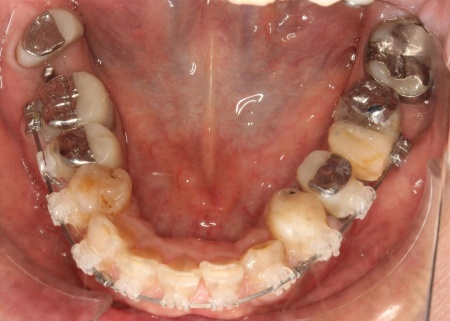

下顎は残根も利用しながら、矯正用の小さなネジ「テンポラリーインプラント(インプラントアンカー)」を顎の骨に埋め込んで固定源とする方法も併用し、歯を移動させました。

矯正期間終了後は、被せ物による治療に移行します。

上顎の前歯2本ずつと奥歯4本(左右中切歯・第2小臼歯・第1大臼歯)、下顎の奥歯7本(左第1小臼歯・左右第2小臼歯・第1大臼歯・第2大臼歯)には、見た目が自然なセラミックの被せ物「ジルコニアクラウン」を装着しました。

加えて、上前歯4本(左右側切歯・犬歯)と下前歯5本(左右中切歯・側切歯・右下犬歯)は、ダイレクトクラウンによる修復を行いました。

ダイレクトクラウンとは、レジン(樹脂)を用いて直接歯の形を作り上げていく治療方法です。

歯を削る量が少ない、色や形を細かく調整しながら仕上げられる、治療後は必要に応じて微調整がしやすいなどのメリットがあります。